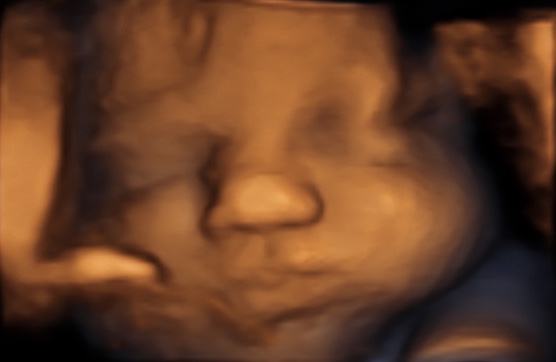

34 weken

Een echo na 34 weken.